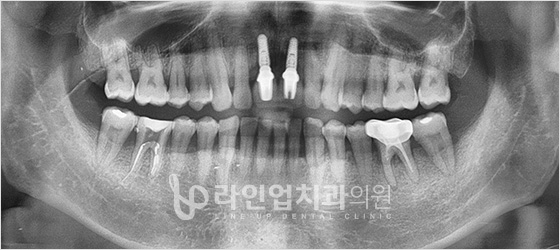

치료전 Before

치료후 After

门牙种植牙